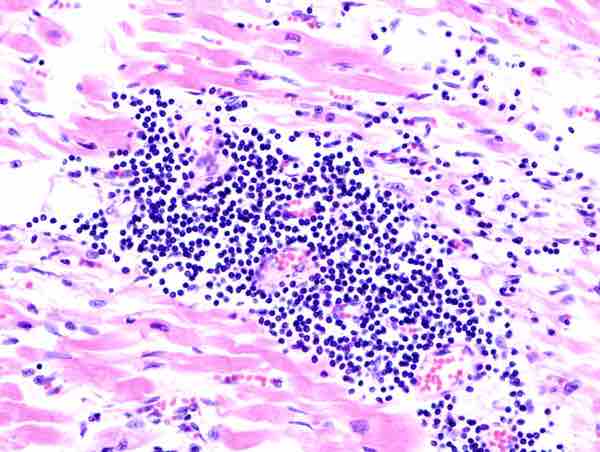

Viral myocarditis

Histopathological image of myocarditis at autopsy in a patient with acute onset of congestive heart failure